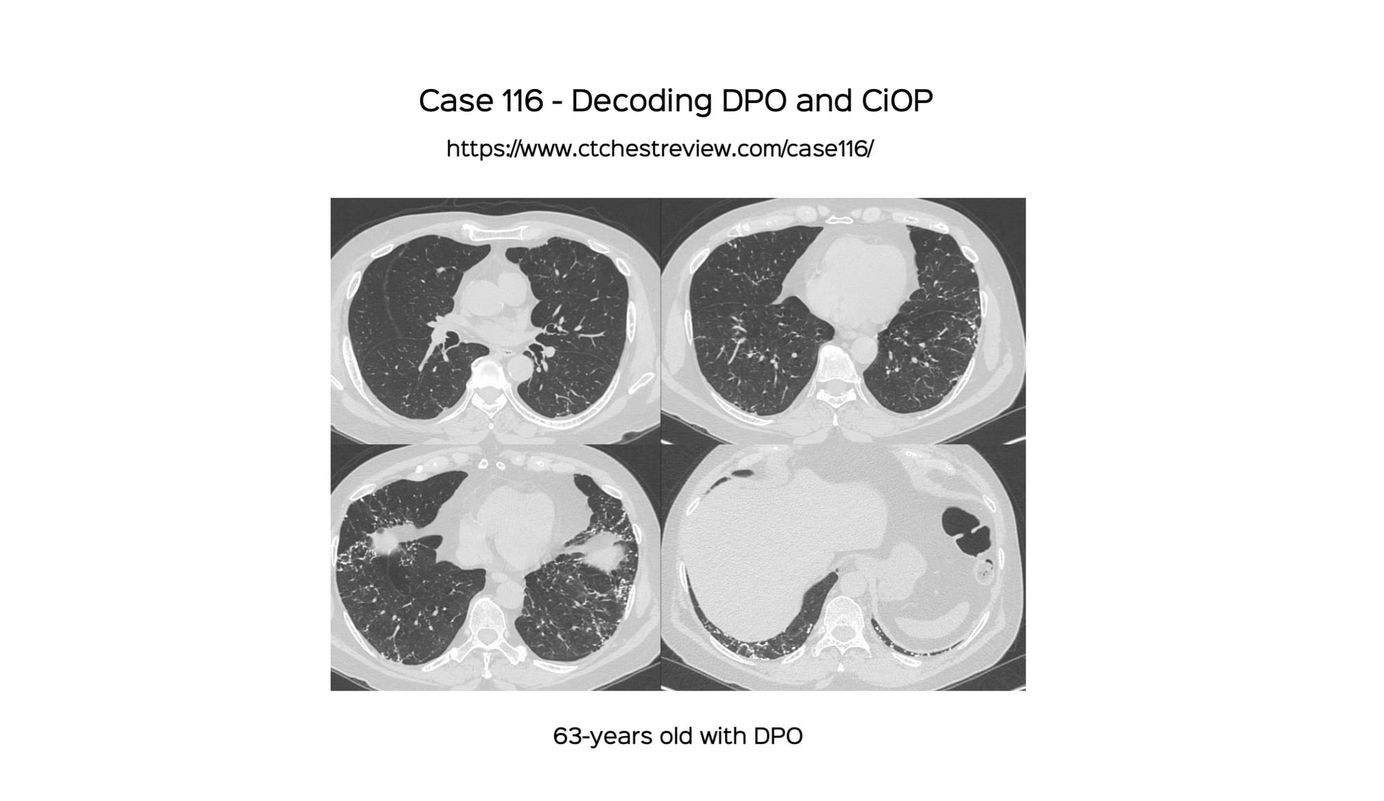

Case 116 - Decoding DPO and CiOP Paid Members Public

DPO is a pattern…of nodular, mixed or dendriform subpleural ossific areas, a CT marker of CiOP, idiopathic or secondary to other fibrosing ILDs. Clinically, this may be an ILA if asymptomatic or part of an ILD if symptomatic.